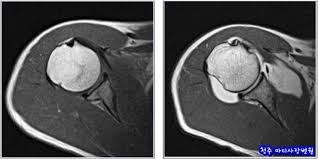

- MRI (자기공명영상): 강한 자기장과 라디오파를 사용해 내부 구조(근육, 뇌, 장기 등)의 단면 영상을 생성합니다. 방사선 노출 없이 해상도가 뛰어나 종양, 염증, 디스크 병변 진단에 탁월합니다 :contentReference[oaicite:1]{index=1}.

| MRI | 연부조직, 장기, 신경, 근육 | 종양, 관절염, 디스크, 뇌출혈, 신경병변 |